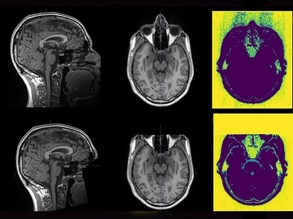

Brain Genes Identified